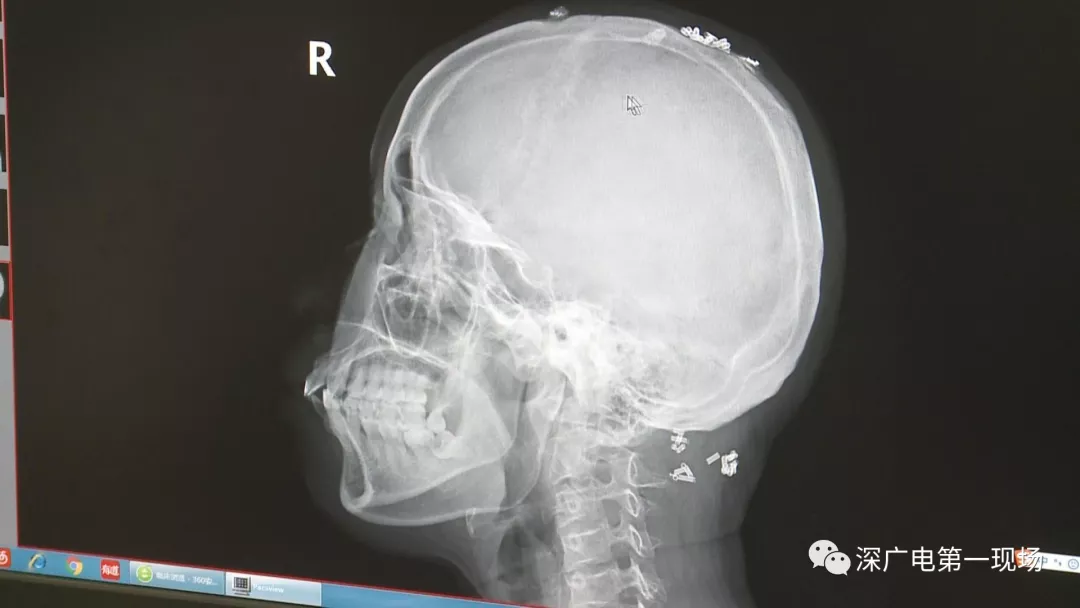

从X光影像图片中可以看到

患者周身布满了弹簧圈

深圳大学总医院神经外科副主任医师陈富勇介绍,当时检查的时候发现,该患者从头部到腿部,基本上每个地方都有弹簧,很难数清具体数目。

陶主任表示,将这些弹簧圈取出也是一项大的工程,因为有的都已经形成了包块,所以想要取出还得先定位,再挨个手术取出,目前医院方面已经将患者头部和颈部的部分取出。